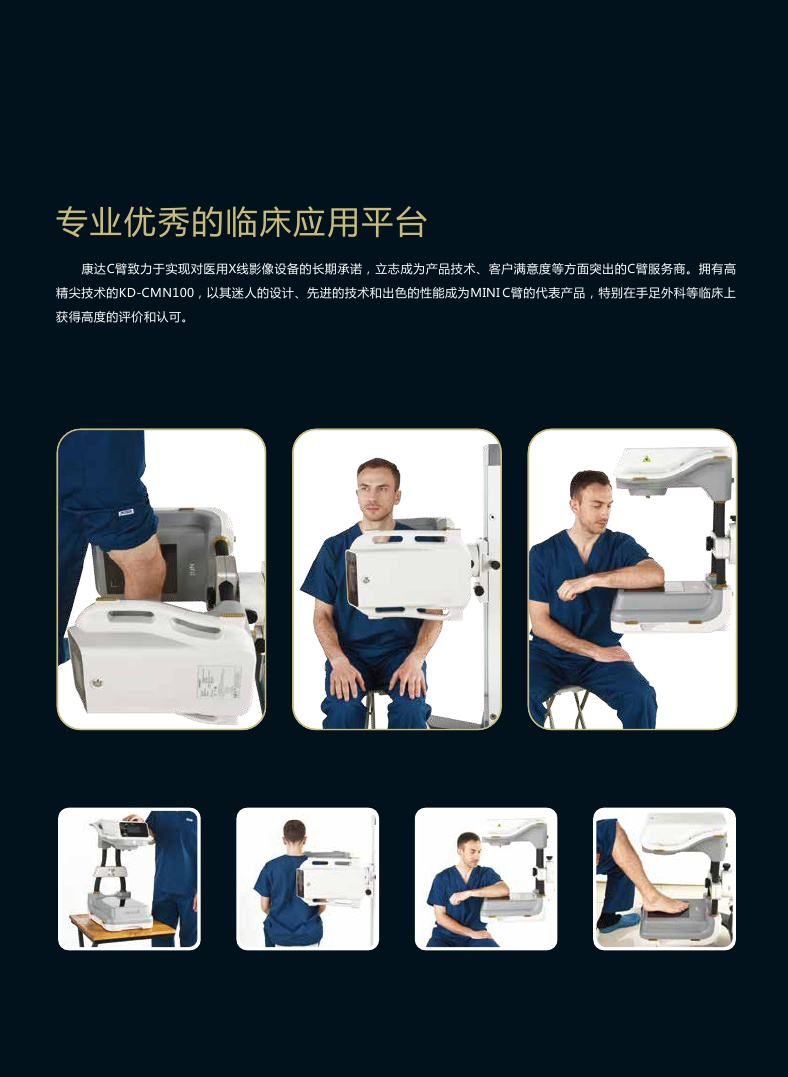

康达 C 臂致力于实现对临床用户的长期承诺,立志成为产品技术、客户满意度等方面最成功的 C 形臂服务商。

拥有高精尖技术的 CMN100,以其迷人的设计、领先的技术和非凡的性能成为便携式 mini-C 的代表产品,在手足外科临床上获得高度的评价和认可。

专业图像降噪算法,使得透视影像媲美专业 DR 图像

图像边缘及对比度强化功能,随时调节图像效果

无失真无畸变成像